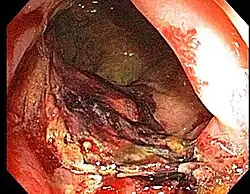

A colonoscopy showing radiation proctitis.

Proctitis has many possible causes. It may occur idiopathically (idiopathic proctitis, that is, arising spontaneously or from an unknown cause). Other causes include damage by irradiation (for example in radiation therapy for cervical cancer and prostate cancer) or as a sexually transmitted infection, as in lymphogranuloma venereum and herpes proctitis. Studies suggest a celiac disease-associated "proctitis" can result from an intolerance to gluten.[1][2]